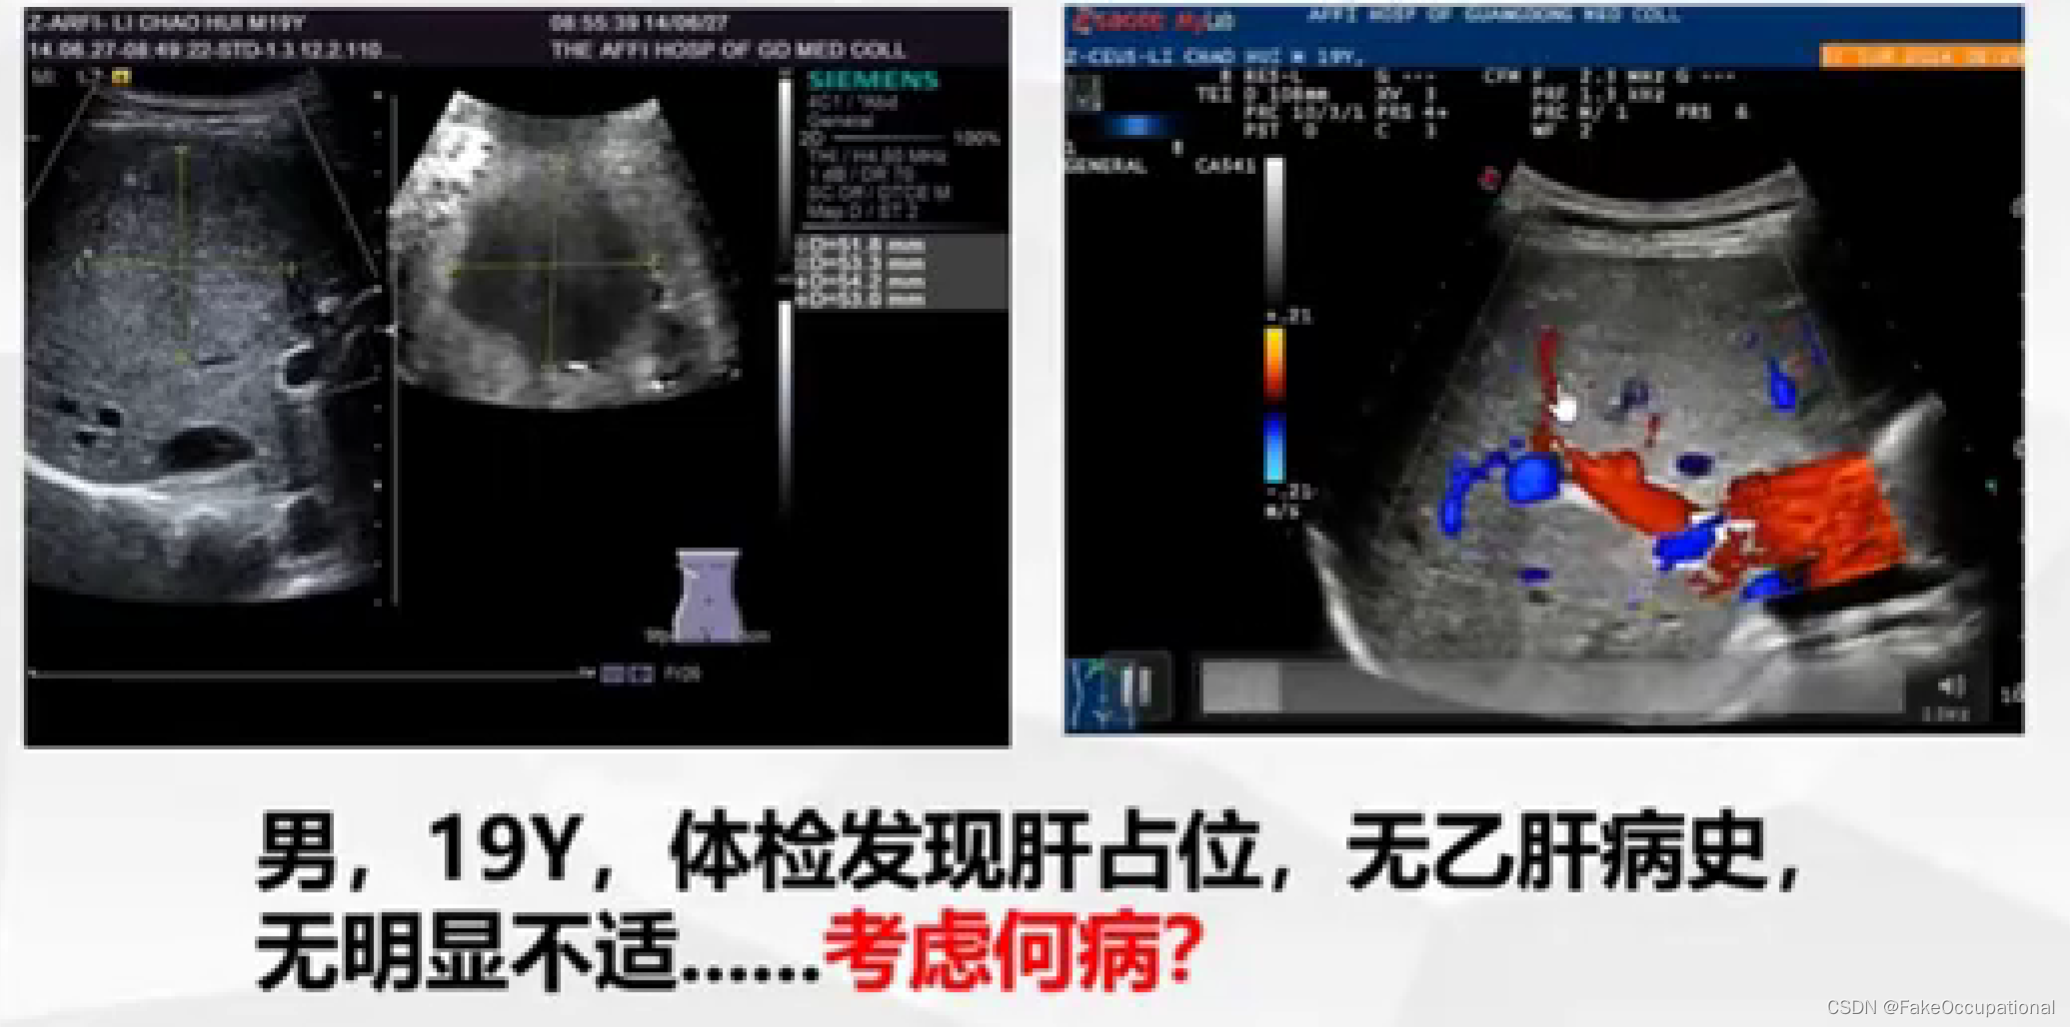

- 彩色编码实时显示血流方向、速度及血流性质:彩色多普勒血流成像(CDFI),彩色多普勒能量图(CDE)

- 超声更多起一个筛查的作用,定性需要造影或者其他设备的辅助